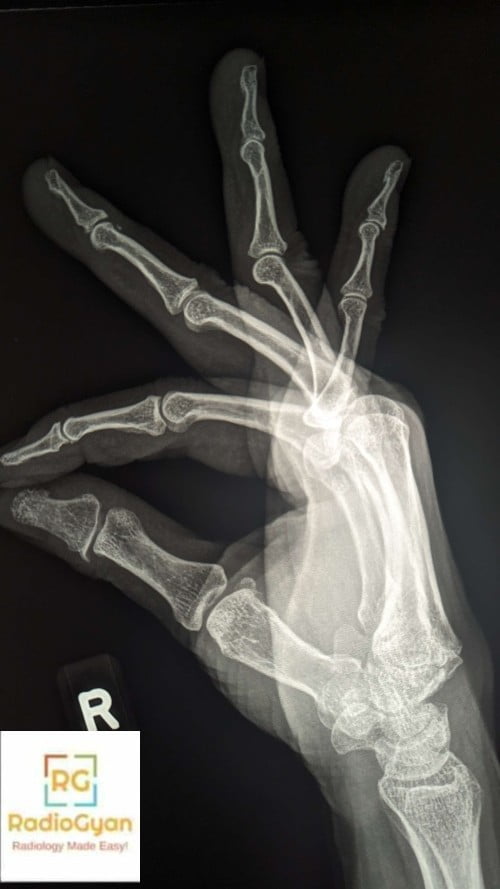

What is the finding on this radiograph?

- Fracture of the lunate bone

- Carpal boss of the metacarpal bones

- Dislocation of the carpal bones

- Normal study

The carpal boss is an osseous protuberance along the dorsal base of the second or third metacarpal, between the trapezoid and capitate. The exact pathogenesis is not known. The proposed causes include degenerative osteophyte formation, sequela of prior trauma, carpometacarpal joint partial or complete coalition, exostosis, an accessory capitate bone, or an accessory ossicle -Os Styloideum located at dorsally between capitate, trapezoid and second and third metacarpal

- Radiograph– AP and lateral wrist radiograph – the presence of a bony protuberance or an abnormal ossicle along the dorsal aspect of the wrist at the base of the second or third metacarpal.

- Carpe Bossu view- a lateral radiograph with the hand flexed and supinated 30-40 degrees for better visualisation of the accessory bone